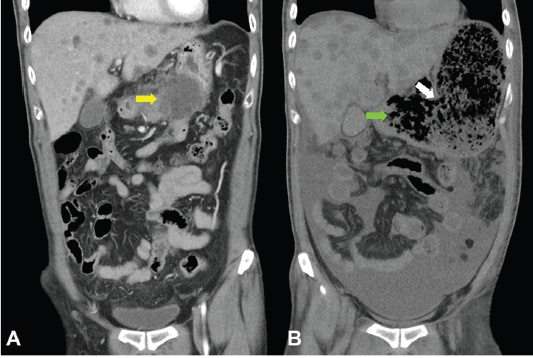

Computed tomography (CT) scan showed a huge heterogenous contrast-enhanced mass at the stomach body abutting and probably invading the duodenum and pancreas with numerous nodules in bilateral hepatic lobes and peritoneal cavity, including perigastric region (Figure 1). The picture was reasonably attributed to an advanced gastric cancer with multiple hepatic and peritoneal metastases.

Figure 1. CT scan showing a heterogenous enhanced gastric mass abutting and probably invading the duodenum and pancreas with multiple metastatic lesions in the liver.

Unfortunately, a catastrophic event did happen 2 days after finishing the first course of chemotherapy. The patient experienced sudden onset of intolerable abdomen pain with hypoactive bowel sounds, muscle guarding, and definitely apparent rebounding pain. An emergent non-contrast CT scan gave a picture of distended stomach fully filled with foods, irregular mottled gas collections between stomach and duodenum, ascites accumulation, and free air in the abdomen cavity, leading to an impression of gastrointestinal tract perforation with the perforation site clearly seen (Figures 6–8). In comparison with CT scan performed at initial diagnosis, it seemed that a severe necrotising tumour lysis induced by chemotherapy, morphologically resembling emphysematous pancreatitis [14–16], could explain the whole scenario logically.

Figure 6. CT scan of the abdomen, horizontal view. A. June 8, 2019. Yellow arrow: the huge gastric tumour. B. July 3, 2019. White arrow: gastric perforation site. Green arrow: Necrotising tumour lysis simulating emphysematous pancreatitis.

Figure 7. CT scan of the abdomen, coronal view. A. June 8, 2019. Yellow arrow: the huge gastric tumour. B. July 3, 2019. White arrow: gastric perforation site. Green arrow: Necrotising tumour lysis simulating emphysematous pancreatitis.